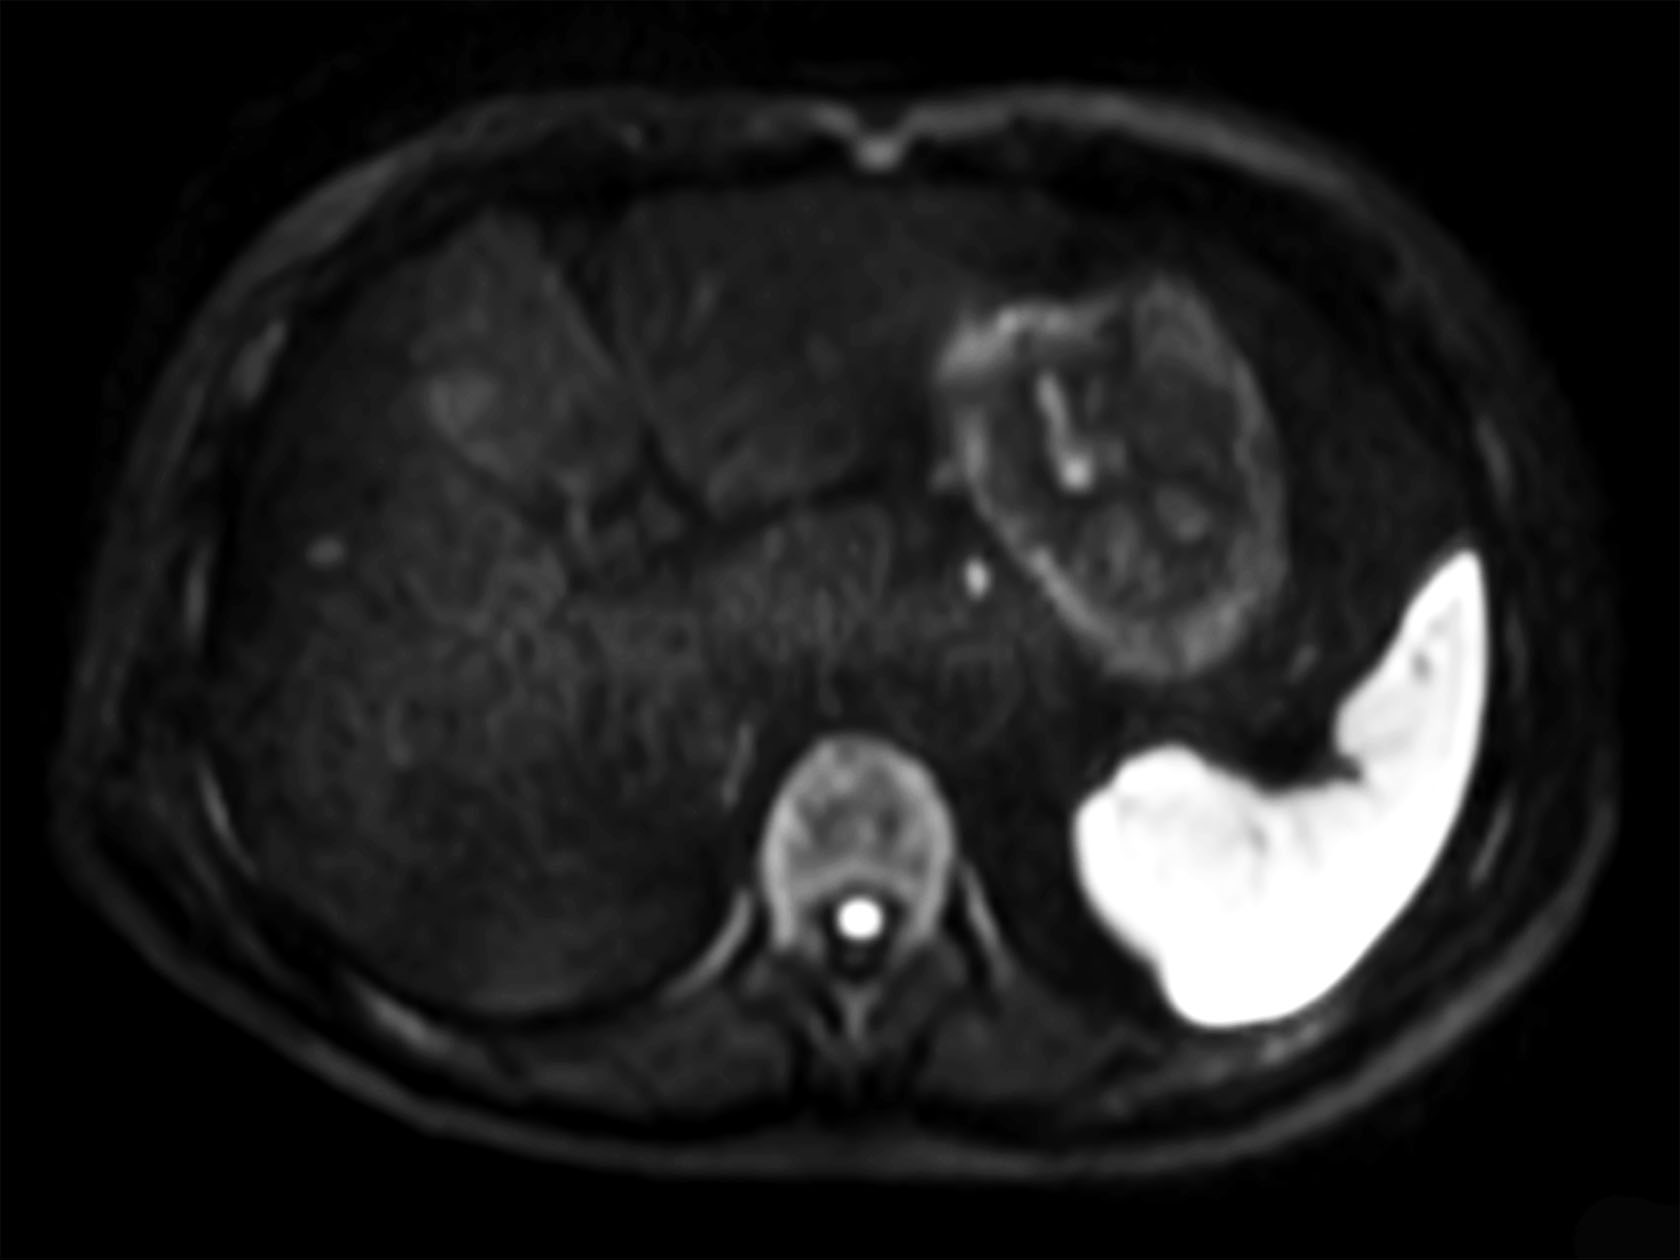

Diffusion (b0)

Diffusion (b1000)

Diffusion (ADC)